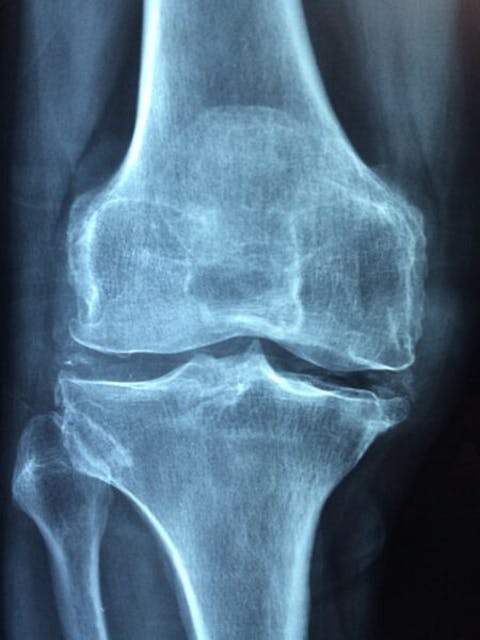

Arthritis is an inflammatory disease that affects joints and causes pain. There are two types – osteoarthritis and rheumatoid arthritis. The first one involves acute inflammation, while the second one is considered an autoimmune disease. It occurs when the immune system targets affected joints, leading to swelling and pain. Fibromyalgia is a type of arthritis or, according to doctors, a chronic form of arthritis. It results in prolonged pain in one or two joints, making the brain hypersensitive to any form of pain. This prolonged pain can lead to additional problems like depression, fatigue, and cognitive issues, and, in some cases, even drug addiction. The worst places to live with arthritis are those who make these symptoms difficult to manage.